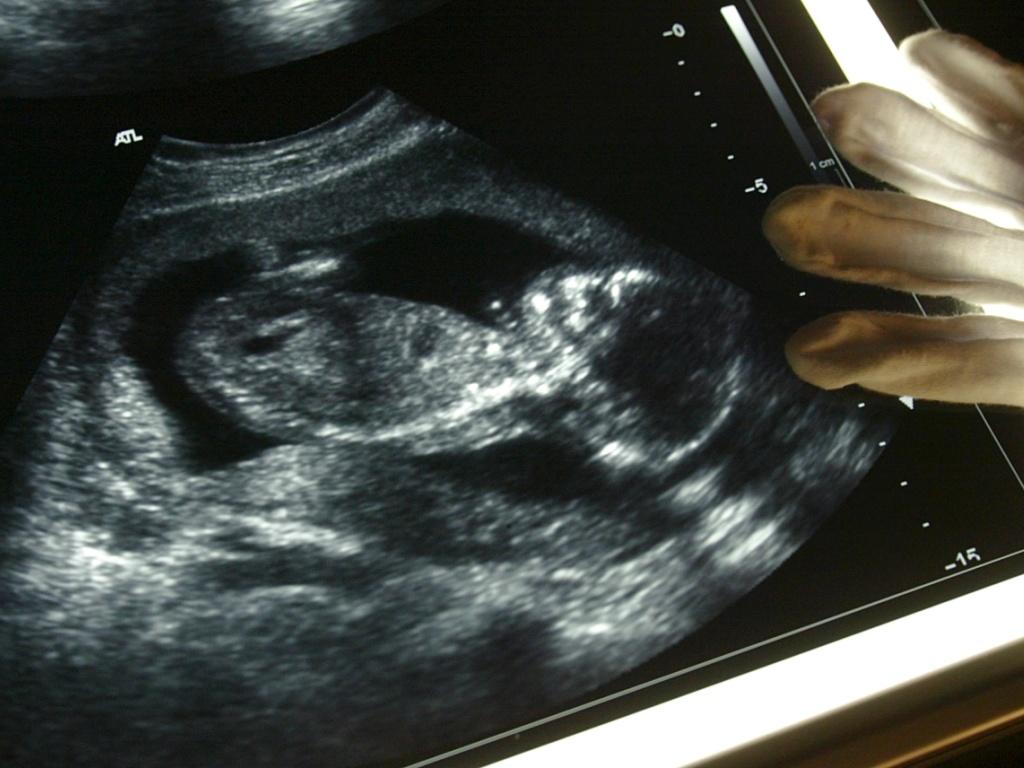

Auch ein Kind, das vor der 22. Schwangerschaftwoche tot geboren wird, soll auf Wunsch der Eltern ein Dokument vom Zivilstandsamt erhalten. Der Bundesrat will so die Trauerarbeit der betroffenen Eltern unterstützen. KEYSTONE/FABRICE COFFRINI sda-ats

(Keystone-SDA) Ab 2019 können Eltern von Fehlgeborenen auf Wunsch ein Dokument einfordern. Der Bundesrat will so betroffenen Eltern die Trauerarbeit erleichtern. Er hat die entsprechende Revision der Zivilstandsverordnung auf den 1. Januar 2019 in Kraft gesetzt.

Die neue Regelung berücksichtige diese Einwände ebenso wie das Anliegen, die Trauerarbeit der Eltern zu unterstützen und die Formalitäten rund um die Bestattung zu erleichtern. Als Fehlgeburt gilt ein Kind, das weniger als 500 Gramm schwer ist und vor der 22. Schwangerschaftswoche tot geboren wird.